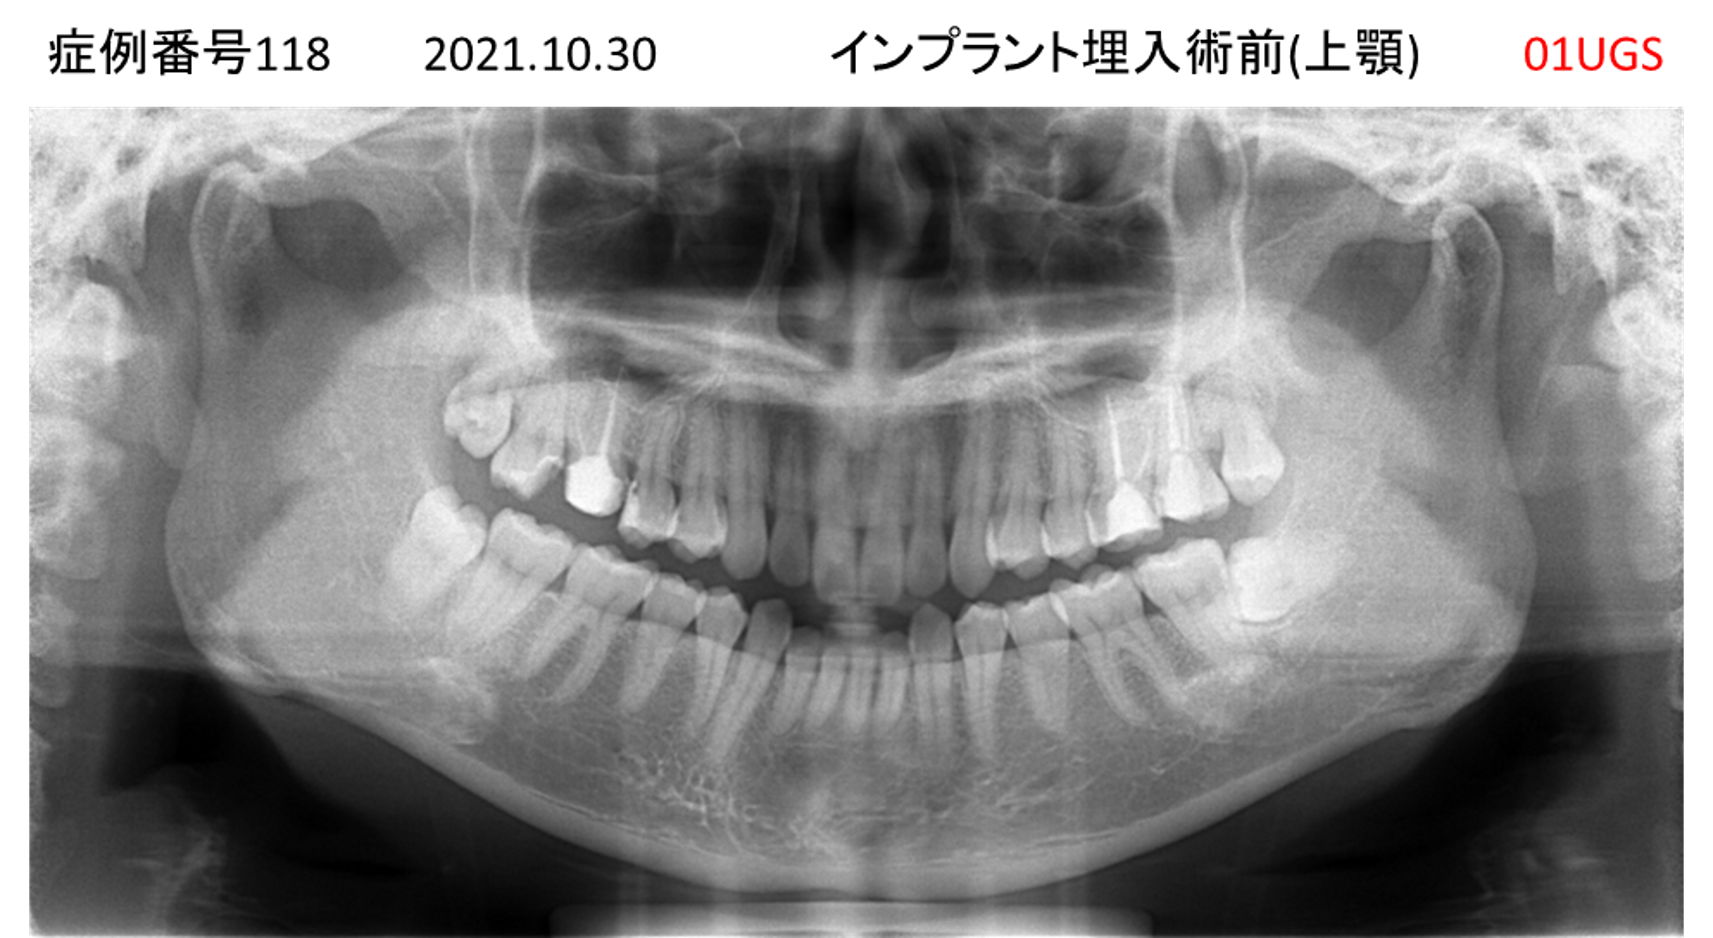

上の前歯が揺れてきてかめない患者様のインプラント症例

| 治療名称 |

インプラント |

| 治療費用 |

440万円+税 |

| 治療期間 |

6か月 |

| 患者さんの症状(主訴) |

上の前歯が揺れてきた。かめない |

| 治療内容 |

サイナスリフト、GBR、インプラント、即時荷重 |

| 治療結果 |

上の前歯の揺れが収まった。奥歯でしっかり噛める。 |

| 治療の注意点(リスク/副作用) |

インプラントが壊れたら再治療が必要 |